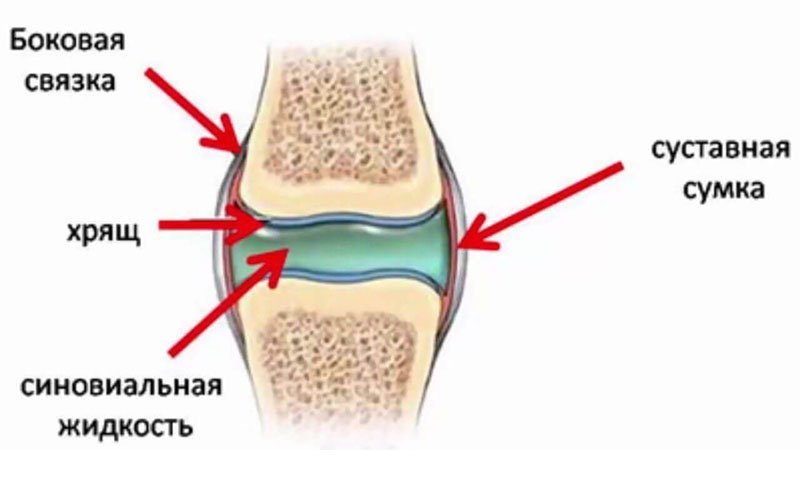

Синовиальная жидкость — это своеобразная природная смазка, которая образуется в суставах и смягчает трение его подвижных частей. Чем меньше смазки, тем быстрее разрушается хрящ. При этом человек чувствует дискомфорт или даже  сильную боль, ограничивается подвижность сустава, область вокруг него может опухнуть.

Импланты представляют собой препараты, замещающие синовиальную жидкость в суставах. Т.е это искусственно созданное синтетическое вещество с высокой вязкостью, которое вводится внутрь сустава. Они изготавливаются на основе гиалуроновой кислоты, которая как раз преобладает в естественной смазке. К таким препаратам относятся ViscoPlus, Рипарт, Синокром и другие.  сильную боль, ограничивается подвижность сустава, область вокруг него может опухнуть.